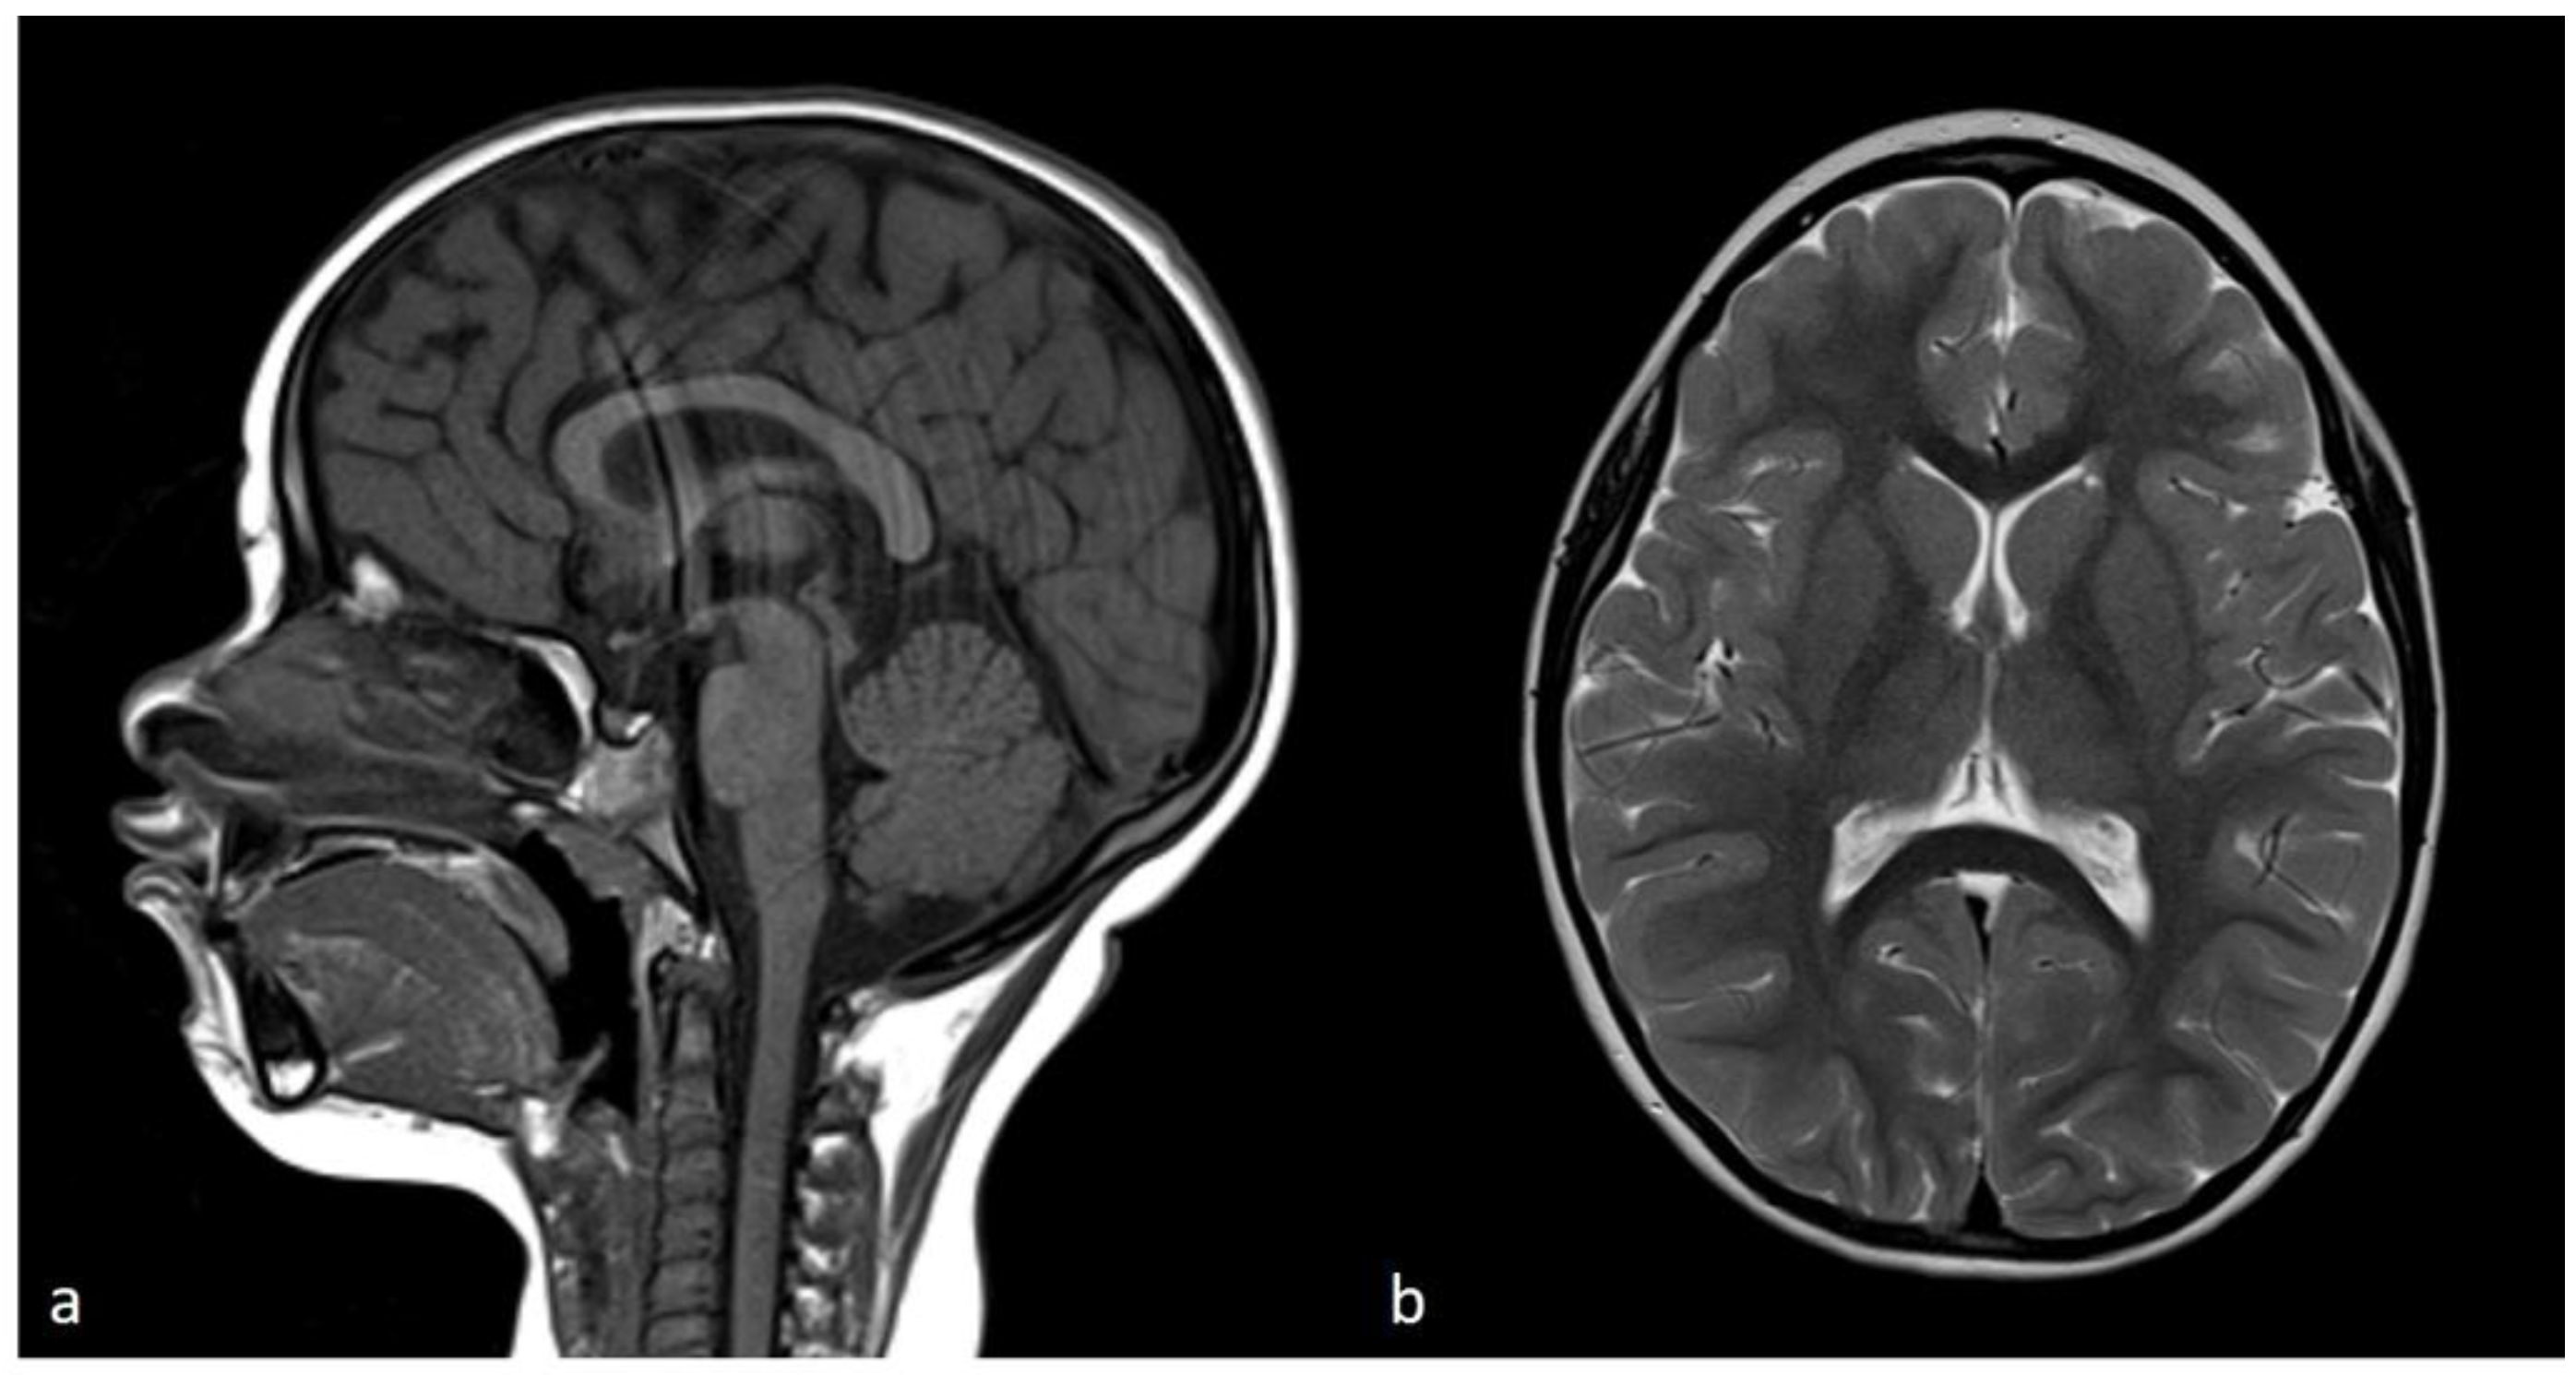

The neuromuscular abnormalities were present shortly after birth through weak cry and poor suck, severe central generalized muscular hypotonia, and absence of deep tendon reflexes. Over the years, the motor milestones were delayed (unsupported sitting at 10 months, standing with support at 22 months, and walking at 30 months). The lack of improvement in hypotonia and deep tendon reflexes was unusual for PWS. Serum creatinine kinase (CK) level was elevated to 5X, a finding not consistent with PWS. Generalized tonic-clonic epileptic seizures with loss of consciousness presented at 3 years of age. CK level was continuously increasing and was elevated to 10X. Magnetic resonance imaging (MRI) of skeletal proximal and distal muscle groups of the lower extremities showed signs of muscle wasting in the proximal extremities and relative sparing of muscles in the distal muscle groups (Figure 2).

Figure 2. Magnetic resonance imaging of skeletal muscles (MRI). Axial T1-weighted images of proximal right and left (a) and distal right and left (b) muscle groups of the lower extremities showed minimal signs of fatty replacement of quadriceps muscles and relative sparing of muscles belonging to the distal muscle groups.